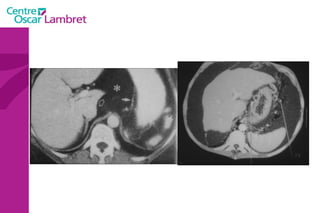

Adénopathies Rétro-cave mésentériques vci

Adénopathies Adénopathies petite courbure

PIEGES ADENOPATHIES ?    TUBE DIGESTIF NON OPACIFIE